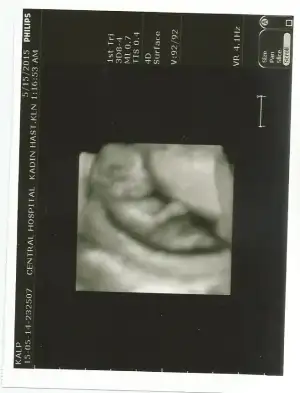

Kıza benziyor bence.Fikri olan var mı acabaEki Görüntüle 1530236

Kiz bence cikinti yokFikri olan var mı acabaEki Görüntüle 1530236

Canım kıza daha çok benzettim ben :)

Canım doktorun erkek dediği resmi de koyar mısın?Bebeğimin cinsiyeti belli oldu ERKEK